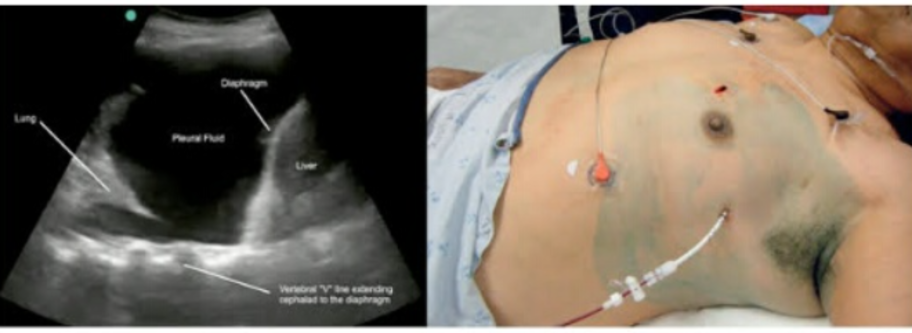

PulmoBLISS Speciality Clinic: Managing Empyema ...